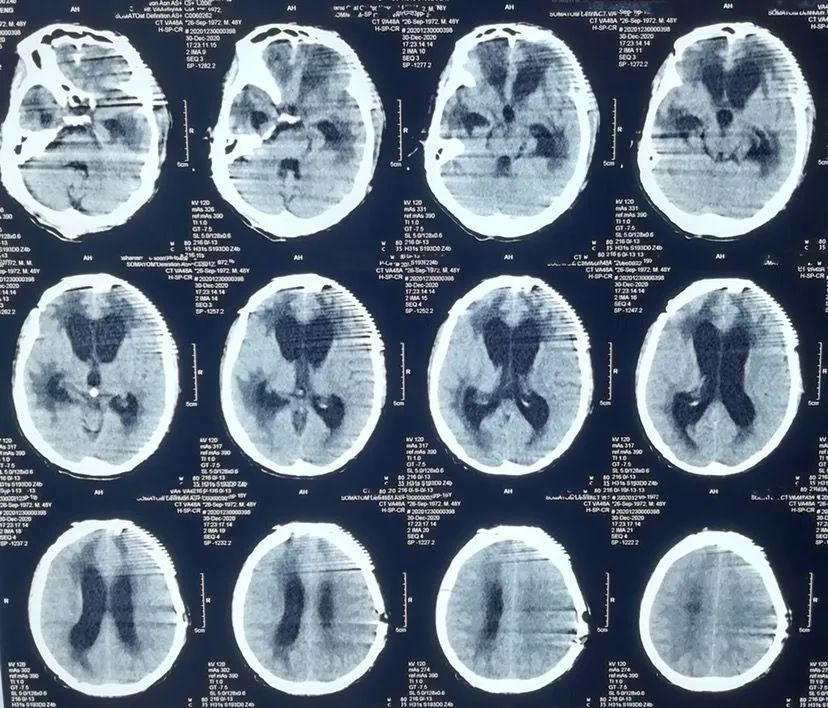

患者男性,48岁。2020年10月头部外伤,头颅CT显示双额叶脑挫裂伤,于当地医院行左额颞开颅血肿清除+去骨瓣减压术。